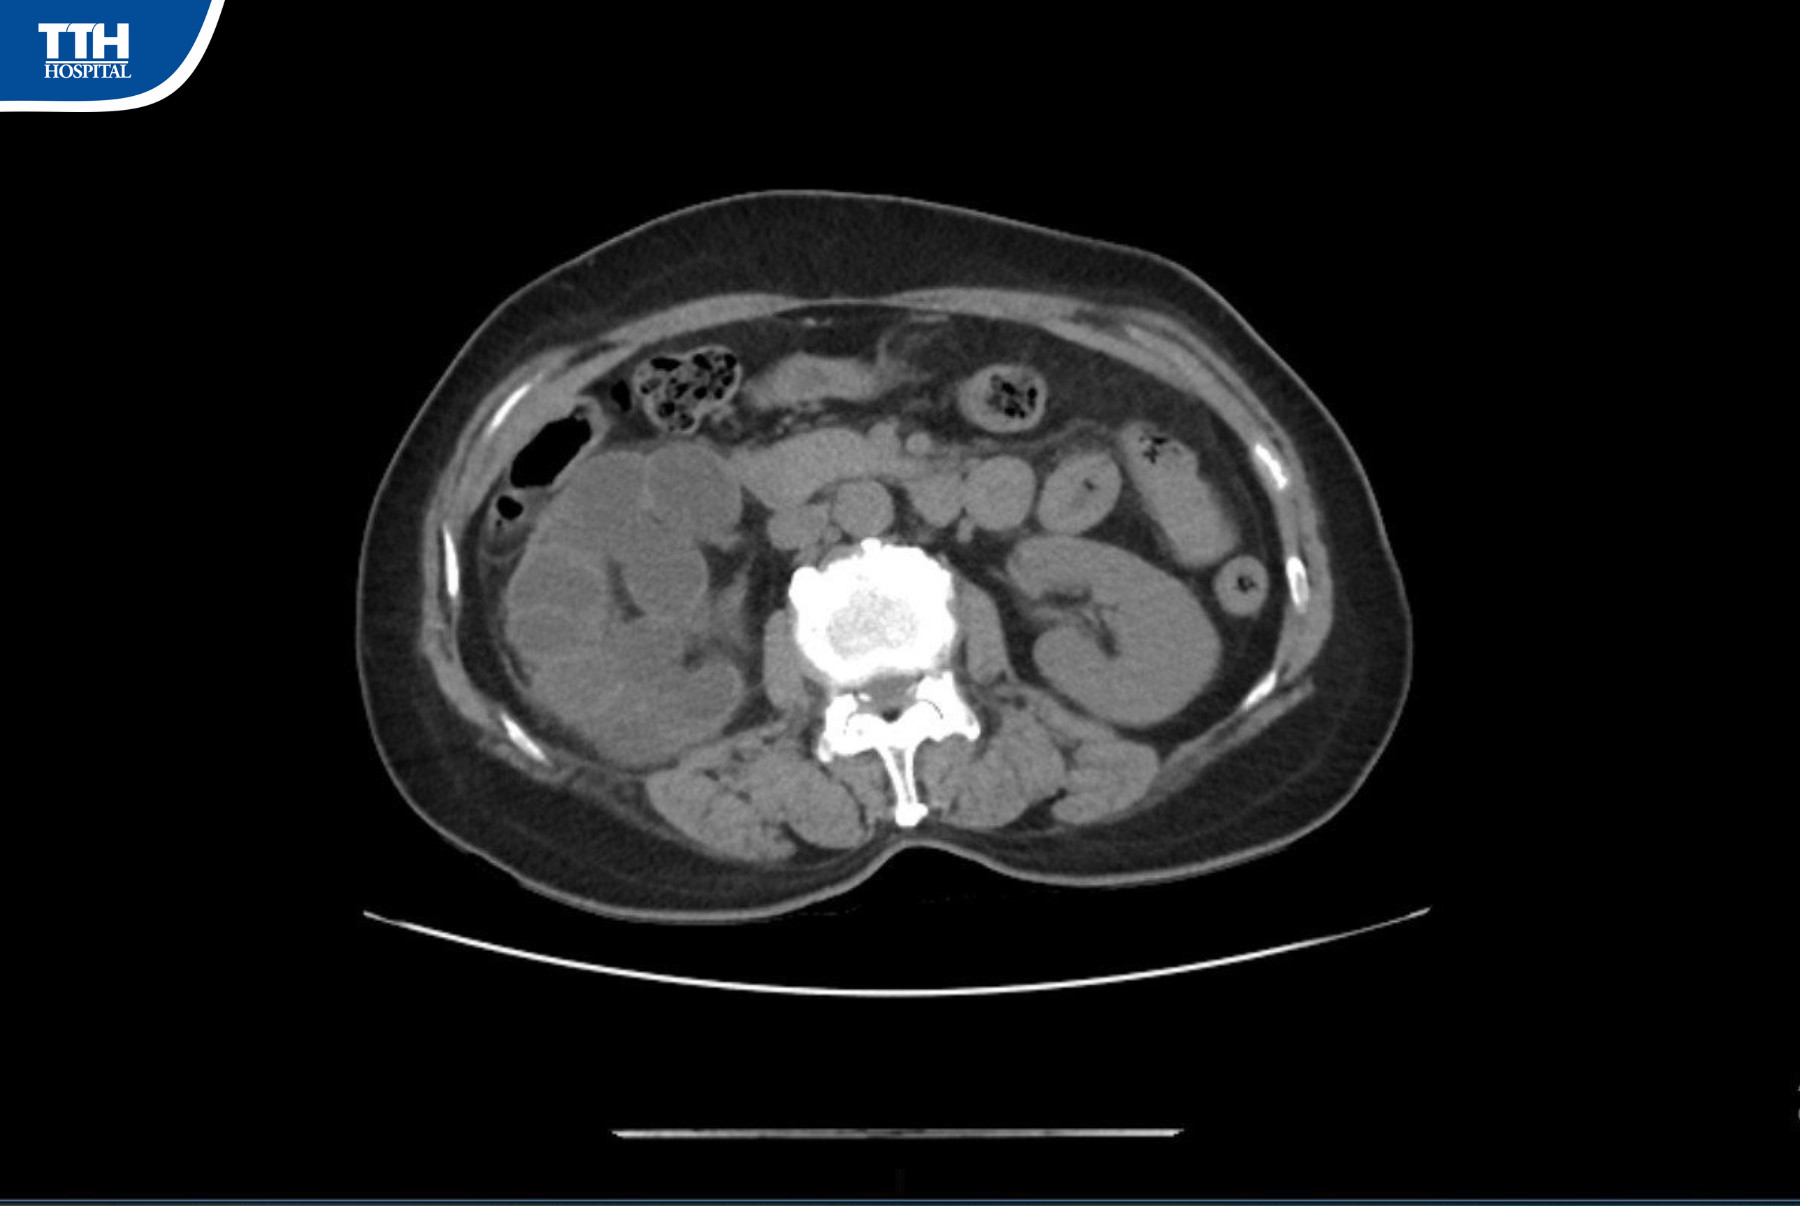

Sau khi tiếp nhận, bệnh nhân đã được làm các xét nghiệm cận lâm sàng. Kết quả xét nghiệm, siêu âm chụp cắt lớp vi tính và xạ hình thận cho thấy thận phải của bệnh nhân có viên sỏi lớn ở khúc nối bể thận niệu quản, thận giãn độ IV, chức năng thận dưới 10%.

Qua hội chẩn chuyên khoa, các bác sĩ khoa Ngoại Tổng hợp chẩn đoán thận phải của bệnh nhân mất chức năng gây nên tình trạng nhiễm khuẩn đường tiết niệu cần phải phẫu thuật nội soi cắt thận phải.